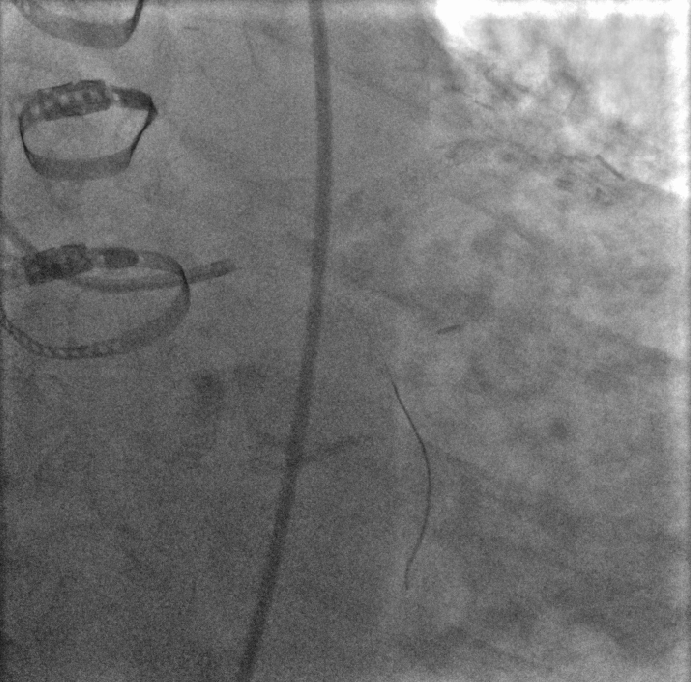

In the work presented here, we develop methods based on image processing to combine the information from fluoroscopic image sequences acquired at different steps of the procedure. More precisely, we consider two types of images: i) the images from reference sequence, which are injected with contrast agent to depict the vasculature and ii) the images from navigation sequence, which are acquired during the navigation of the tool and especially the guide wire, which is navigated from the ostia of the coronary artery down to the distal part after crossing the lesion. The imaging of the vessel with contrast agent provides information on the potential location of the stenosis. The ECG of the patient is recorded along with the images. Standard algorithm as [4] can then be used to identify the subset of the images where the coronary images are well opacified with the contrast agent. In this subset, a reference sequence of about 10 to 15 images is then selected that covers a full cardiac cycle and includes best opacified images. The navigation sequence is obtained with a low dose acquisition mode called fluoroscopy. The guidewire, a very thin (wire-like) object of diameter 0.014′′superscript0.014′′0.014^{\prime\prime} has two sections. The distal section, called as the tip, is more important and is enough radio opaque to be seen with low dose X-ray mode. Our aim is to automatically identify navigation sequence and determine the vessel-of-intervention which is going to be treated in the following steps of the PCI procedure, such as lesion reparation with angioplasty balloon, stenting, post-dilatation.

Tip candidate extraction. Guidewire tip appears as contrasted thin and elongated object in the fluoroscopic image. We are interested to segment the guidewire tip, using a component tree called min tree. The min tree [9] structures all the connected components of the lower-level sets of the grayscale image based on inclusion relationship. We assign to any connected component C𝐶C of the min tree \mathcal{M}, a shape attribute characterizing the shape and structural properties of guidewire tip. Then, the considered attribute 𝒜𝒜\mathcal{A} describes the elongation of the components. For any component C𝐶C𝒜(C)=(π×lmax(C)2)/|C|,𝒜𝐶𝜋subscript𝑙𝑚𝑎𝑥superscript𝐶2𝐶\mathcal{A}(C)={(\pi\times{l_{max}(C)}^{2})}/{|C|}\enspace, where |.||.| represents cardinality and lmax(C)subscript𝑙𝑚𝑎𝑥𝐶l_{max}(C) is the length of the largest axis of the best fitting ellipse for the connected component C𝐶C. Since the guidewire tip is thin and long, the component corresponding to the tip have high value of attribute 𝒜𝒜\mathcal{A}. A mere thresholding of the elongation 𝒜𝒜\mathcal{A} is not sufficient, often giving other long and elongated (unwanted) objects like pacing lead and filled catheters. Indeed, these objects have higher elongation value than the guidewire tip. Hence, according to physical properties of the guidewire tip, we set a upper bound value tmaxsubscript𝑡𝑚𝑎𝑥t_{max} on 𝒜𝒜\mathcal{A} to maximum possible elongation value of the guidewire tip, to ensure that extracted components contain guidewire tip. Even with this upperbound threshold keeping the most elongated component does not always lead to the desired tip. Based on min tree structure, the nested connected components that satisfy the criterion are filtered to preserve the component with largest area (taking aid of the inclusion relationship). Therefore, we adopt the shaping framework [10] that allows us to efficiently extract significant connected components. The extracted components constitute the tip candidates. Shaping extensively uses the min tree structure to regularize the attributes and to select the relevant components. In order to facilitate matching, we perform skeletonization [3] of the selected connected component(s) to obtain centerline of the tip candidates. Fig. 1 shows the obtained centerline of segmented guidewire tip from the input image. This centerline of the tip candidate 𝒞𝒞\mathcal{C} is modeled as a discrete polygonal curve.